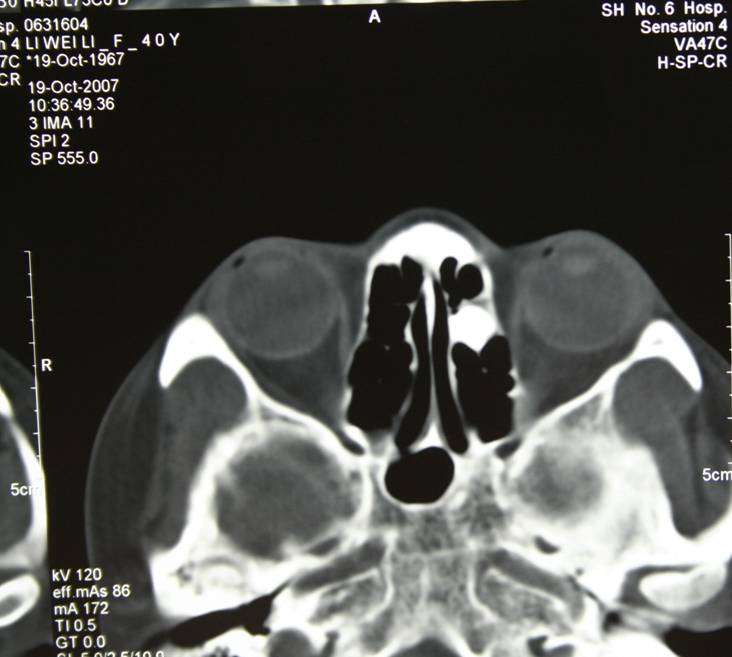

骨纤维异常增殖症又称为骨纤维结构不良,属先天性骨组织异常增殖的病变。被认为是一种从原始骨到板层骨改建障碍而导致的发育病变。骨骼发育障碍造成不成熟的孤立骨小梁遗留在发育异常的纤维组织中。这些骨小梁代谢缓慢,不能重塑骨骼形态。不成熟的骨基质可导致非正常的矿化过程。缺少对外力的调整和矿化不全共同导致了骨骼机械强度的丧失。进而出现疼痛、畸形或者病理性骨折过程

畸形明显者,应采取积极的治疗措施,纠正或阻止功能性畸形的发展,改善面部外观。一般采用削除术、剜刮术或颌骨部分切除术治疗。我们采用骨纤维异常增殖的内镜经鼻微创治疗,减少手术并发症及手术瘢痕;由于内镜入路具有较好的视野.可避免面部切口同时最大程度切除病灶,优于传统手术方法。

骨瘤标本